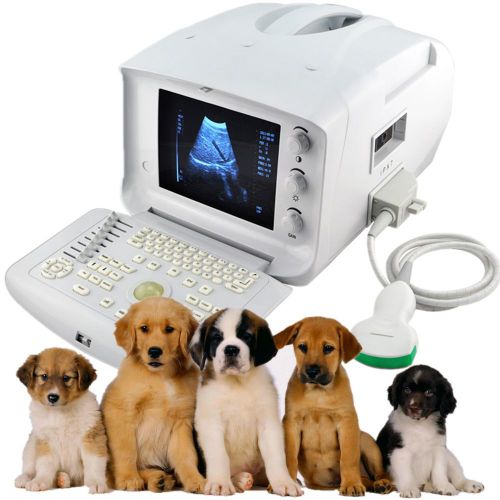

VET Portable Ultrasound Scanner with Rectal Probe for Veterinary+ 3D software CE

CE VET Veterinary Portable Ultrasound Scanner with convex Probe+ Free3D software

2015 CE VET Portable Ultrasound Scanner with convex Probe+ Free 3D software